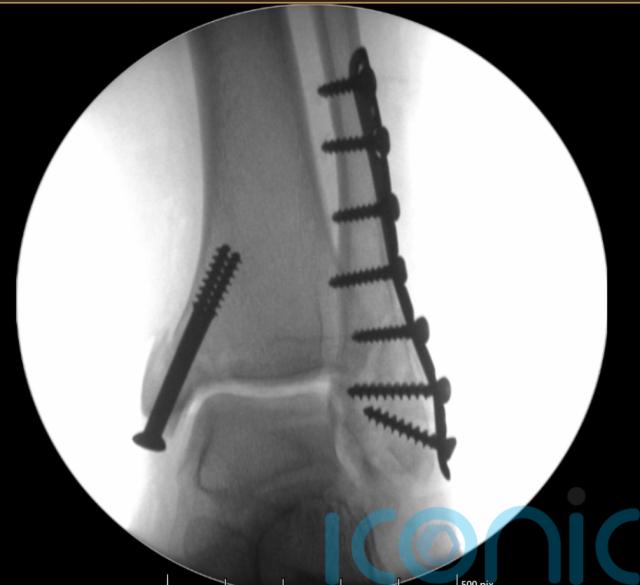

She underwent two rounds of surgery to rebuild her ankle with metal pins and plates before being discharged five days later.

“In December 2019, I had another operation to remove some of the metal work in my foot,” she said.